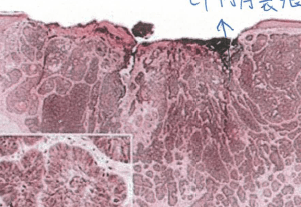

一般我自己心裡面想的疣應該比較偏向雞眼的方向,這東西是由 Poxvirus,就是痘病毒的其中一個支線(MCV Virus) 所產生出來的Paupule,出生後會自己退掉

免疫抑制, 新生兒,組織切片裡面角化細胞腫脹(因為每個keratin cell 裡面都是病毒體),一開始這些病毒體是紅色,後來變成藍色 (erosinphilic to basophilc )